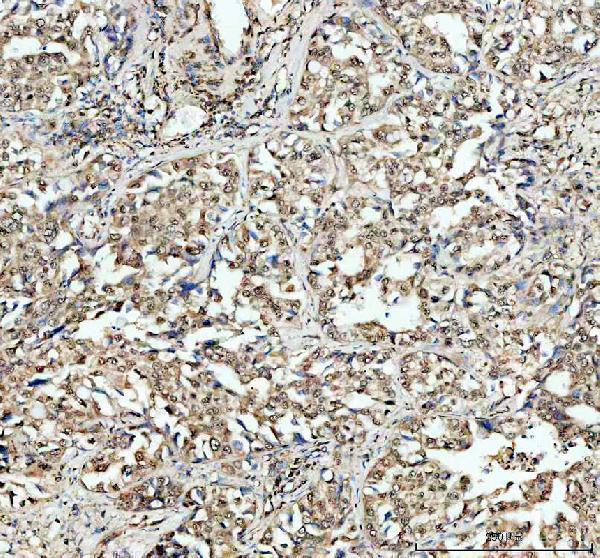

Expressed in cartilage, spleen, intestine, lung, and to a lesser extent in heart, brain, liver, muscle and stomach.

Cytoplasm. Nucleus. Predominantly localized in the nucleus (PubMed:11278694).